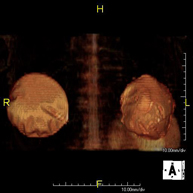

- RM Hombro

Exploración para el estudio de lesiones en tendones, músculos y articulación. Su principal utilidad reside en diagnosticar las lesiones de los tendones del manguito rotador. Tiene una duración aproximada de 20 minutos. No emplea radiación ionizante.